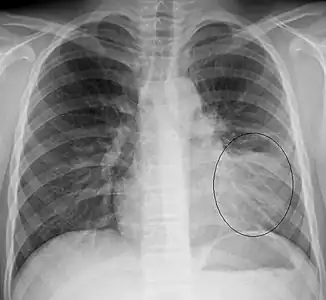

AP CXR showing left lower lobe pneumonia associated with a small left sided pleural effusion -

AP CXR showing right lower lobe pneumonia -

AP CXR showing pneumonia of the lingula of the left lung -

Right upper lobe pneumonia as marked by the circle. -

Left upper lobe pneumonia with a small pleural effusion.